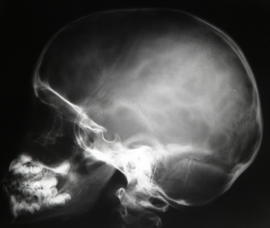

O que pode ser bem visualizado no Rx P?

Região frontal e Parietal.

Hipófise, Sutura Occipital, Sulco da Artéria Meníngea Média.

Como avaliamos se uma Rx P foi bem feita?

Os ângulos mandibulares devem estar bem sobrepostos, alinhados.